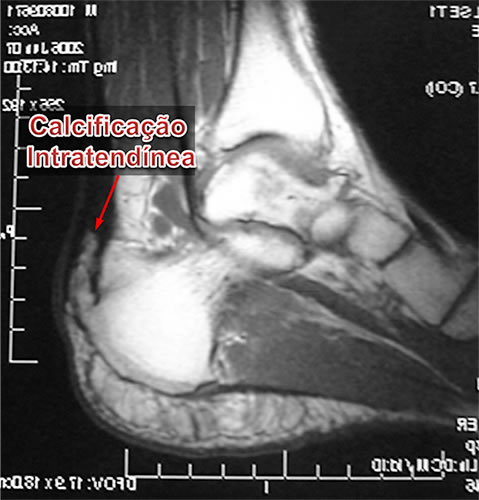

- Calcificação Intratendínea (Esporão do Tendão de Aquiles)

A calcificação intratendinea, popularmente chamada de esporão do tendão de Aquiles, forma-se por uma alteração celular degenerativa das fibras do tendão. Isto ocorre pela alternância, durante um longo período de tempo, entre os processos de inflamação, micro ruptura e reparo local. Portanto, a constante tentativa de cicatrização de uma lesão crônica do tendão leva à sua degeneração e calcificação local de suas fibras.

Embora a ultrassonografia seja útil no diagnóstico de doenças tendíneas, a ressonância nuclear magnética é o melhor exame para avaliar as condições teciduais do tendão de Aquiles, possibilitando visualizar o grau e a extensão do processo degenerativo, calcificações e pequenas rupturas com melhor definição e maiores detalhes.